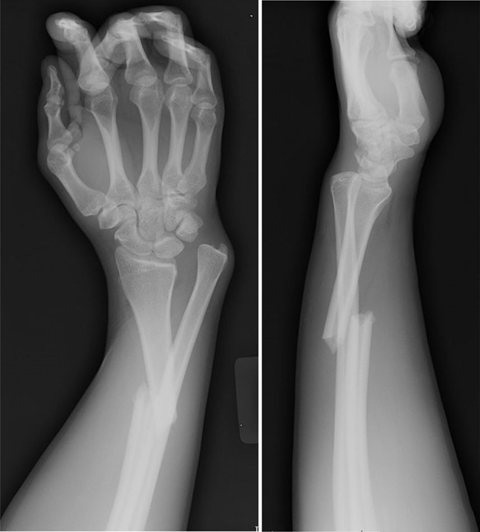

(5)Galeazzi 骨折

盖氏骨折,又称 Galeazzi 骨折,是桡骨干下 1/3 骨折合并下尺桡关节脱位,是一种既有骨折又有脱位的复合损伤,是一种极不稳定的骨折。